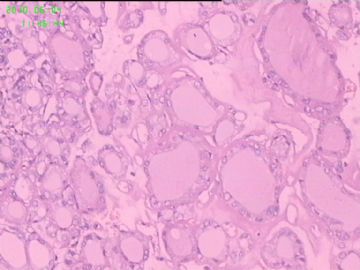

灰白结节2枚,其一2.5x1.8x1.5cm,包膜完整,内为褐色胶质,其二3x2.5x1.5cm包膜完整,切面灰白实性。附件镜下为后者。

可能楼主看到那些核的变化吧?但是没有其他支持的条件,还是应该是结甲。

要看肿瘤包膜情况。